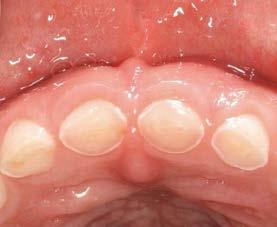

Tras 6 meses de oseointegración, se procedió a la confección de la prótesis definitiva. En aquel momento, hace 22 años, se eligió un biopilar microfresado y una corona metal-cerámica cementada, que representaban la mejor alternativa para garantizar un sellado adecuado y una estética satisfactoria en el sector anterior. En la actualidad, la opción preferible habría sido una prótesis atornillada con un elemento intermedio (transepitelial unitario) y una corona totalmente cerámica cementada a una interfase. No obstante, es importante contextualizar la decisión en función de la época en la que se finalizó el caso (Figuras 12 y 13).

La paciente ha permanecido en seguimiento y mantenimiento clínico durante 22 años, sin evidenciarse pérdidas óseas periimplantarias ni recesión gingival en torno al perfil de emergencia (Figura 14). En la actualidad, se realizó

Estos hallazgos confirman el éxito del procedimiento quirúrgico y de la posterior carga progresiva, con un mantenimiento óptimo de los tejidos duros y blandos a lo largo de más de dos décadas (Figura 15). Los cambios entre el momento inicial y el final del tratamiento son evidentes, especialmente al comparar la imagen intraoral de la primera visita con la tomada a los 22 años, donde la mucosa que rodea al diente 21 —y posteriormente al implante— se muestra engrosada, en buen estado de salud y con una estética destacable. Asimismo, la comparación entre la radiografía inicial, que evidenciaba el fracaso del tratamiento de conductos del diente en posición 21, y la radiografía a los 22 años, que muestra el implante sin pérdidas óseas asociadas, resulta elocuente (Figuras 16 a 19).

Figuras 16 y 17. Comparación entre la imagen inicial —diente con cambio de coloración, encía inflamada y pérdida de grosor— y la obtenida a los 22 años, que muestra estabilidad y salud gingival con el implante.